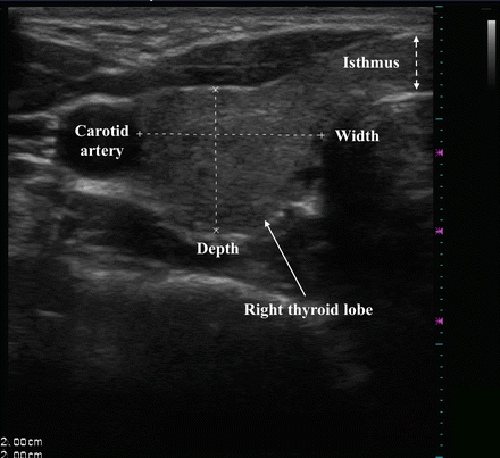

Thời gian gần đây, cảm thấy cổ họng hơi vướng khi nuốt, giọng khàn hơn, sờ vào cổ thấy nổi một khối mềm, chị L mới vội vàng đi khám. Tại Bệnh viện Hồng Ngọc, qua thăm khám bác sĩ Nguyễn Thị Ngọc Thắng – chuyên khoa Nội tiết chẩn đoán xác định chị có u nang tuyến giáp đơn nhân kích thước 2x2cm, mật độ mềm, ranh giới rõ, di động nheo nhịp nuốt.

Hình ảnh siêu âm u tuyến giáp của bệnh nhân |

Để chắc chắn về tính chất khối u, chị Linh được bác sĩ chỉ định sinh thiết tế bào khối u. Kết quả cho thấy u nang tuyến giáp của chị là lành tính. Bác sĩ Thắng tư vấn chị Linh điều trị đốt u bằng vi sóng TATO.

Chị Linh được gây tê cẩn thận vùng cổ trước khi đốt u. Tiếp đó, đầu điện cực của máy TATO được đặt xuyên qua eo tuyến giáp vào tới trong nhân giáp dưới hướng dẫn của siêu âm và bác sĩ Tuấn bắt đầu thực hiện đốt u. Sau 15 phút đốt, u tuyến giáp của bệnh nhân đã được loại bỏ. Nghỉ ngơi 1 tiếng tại viện, chị Linh đã có thể trở về nhà trong trạng thái sức khỏe bình thường.